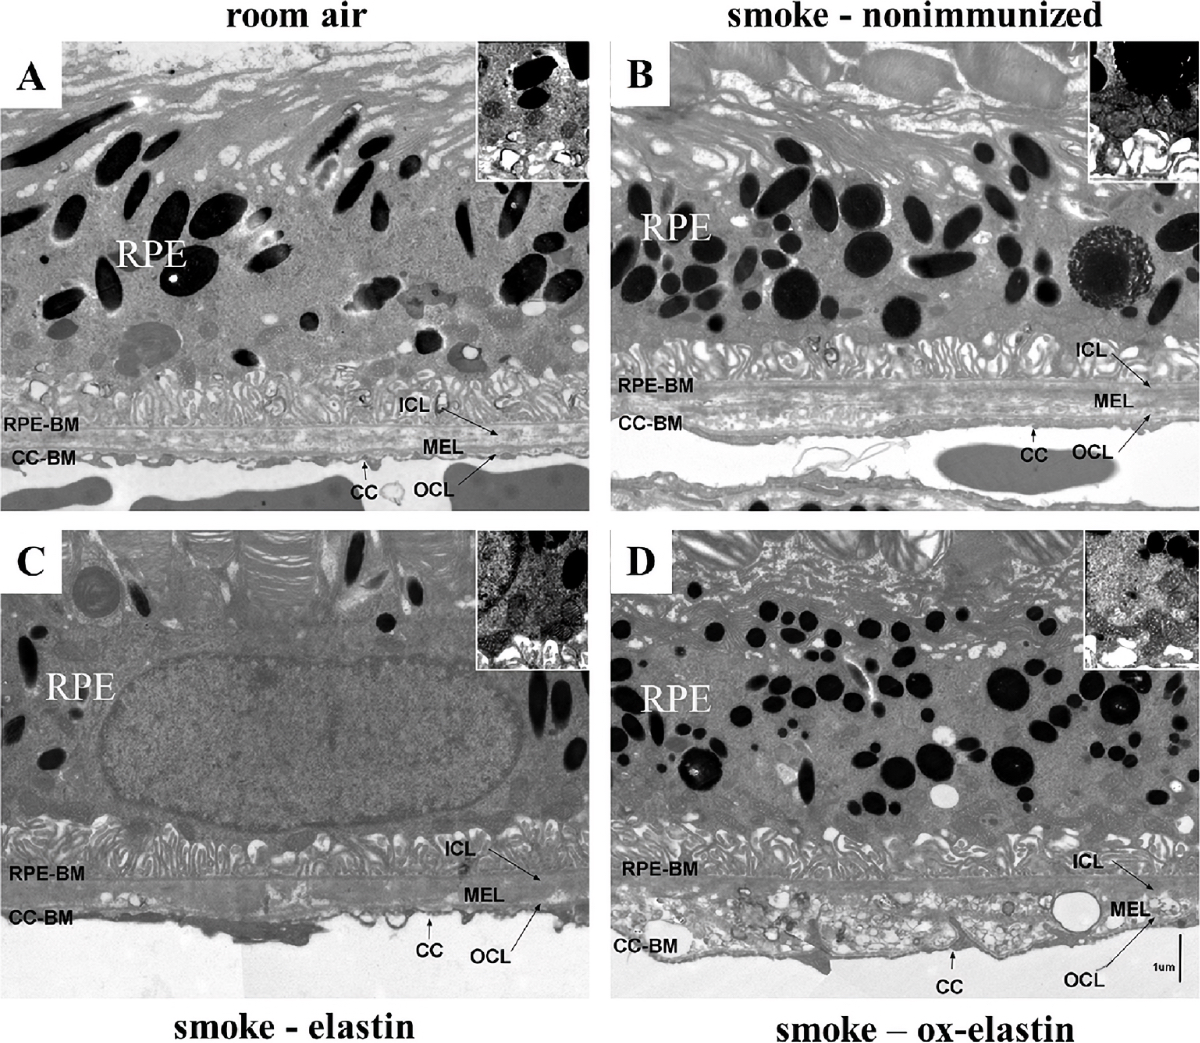

The Alternative Complement Pathway Deficiency Amerliorates Chronic Smoked-Induced Functional And Morphological Ocular Injury

The Alternative Complement Pathway Mediates Functional And Morphological Deficits In A Smoke Model Of Age-Related Macular Degeneration